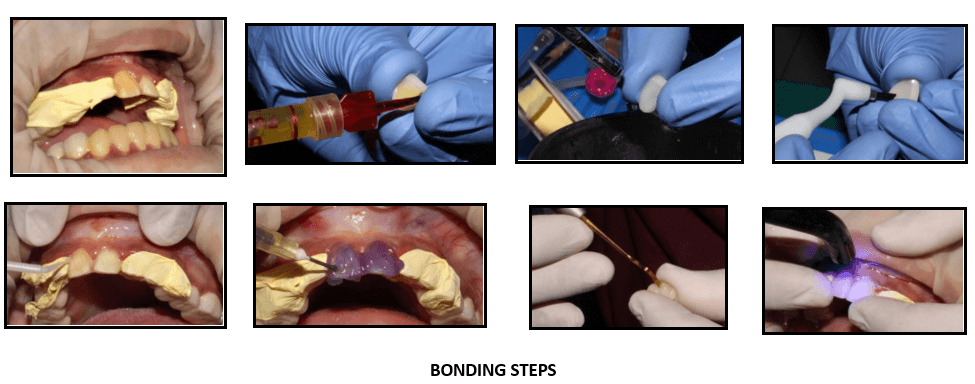

Calibra esthetic resin cement was used for the bonding of laminates.

Thoroughly clean all internal surfaces of the veneer with water spray and Etch the surface of the restoration with porcelain etch. Clean with water spray and dry.

Apply calibre silane to the Air dry the silanated surface of the restoration. Apply a single coat of Prime and bond NT adhesive to the internal surface of the veneer. Air dry for 5 sec. Light cure adhesive for 10 sec

Apply Prime & bond adhesive to tooth surface. The surface should remain wet for 20 sec. Gently air dry for 5 sec. light cure adhesive for 10

Dispense the desired calibra veneer Apply it on the veneer. Protect cement from exposure to light.

Seat the Tack the restoration in place by briefly light curing the gingival portion only for no more than 10 seconds. Remove excess cement.

Light cure all marginal areas for 20 seconds from each direction – buccal, lingual and interproximal

Removal of excess cement flash and finishing of the margins if